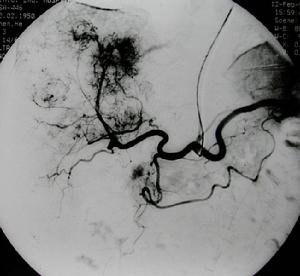

3、血管造影或數字減影血管造影(圖1)它可以提供最為詳盡準確的病情資料,例如病變部位、範圍程度為血管成形手術或手術方式的選擇提供依據。